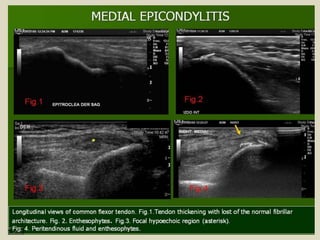

Medial epicondylitis also known as “golfer elbow” is

an overuse syndrome of the common flexor tendon. It is

thought to be due to repetitive micro trauma and results

in fibrosis. The ultrasound findings are comparable with

those of lateral epicondylitis.